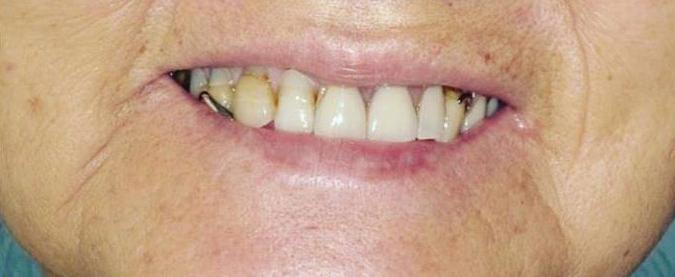

Submitted By Sivakumar Sreenivasan, DMD, MDS Dental Implant Center of Rockville

Can just four implants replace all of the teeth on the top or the bottom of your mouth? Thanks to advances in dental implant technology, that answer is a resounding yes.

Tooth loss is extremely common among adults, especially as we age. Rather than living with the discomfort and hassles of dentures, many people are opting for what is called “all-onfour” dental implant restoration.

An implant is a small titanium

screw that fits inside your jawbone and replaces the root-part of a missing tooth. Minor surgery is required to insert the implants. Once the implant is in place, a crown is attached to give you a highly realistic-looking and functional prosthetic tooth.

You do not need a dental implant for each and every one of your missing teeth. All you need is four precisely placed implants on the top of your mouth, and four on the bottom, to restore your full smile. That’s the beauty of the all-on-four. And because the implant is made of titanium, it has the unique ability to fuse to living bone and function as part of it. So eventually, the dental implant becomes part of the jawbone and serves as a strong, longlasting foundation for your new teeth.

Besides ensuring that your implants are permanently fixed in place, this bone fusion has another important benefit: it prevents future bone loss in the jaw. This helps to maintain a more youthful facial structure – and better

Please see “All-On-Four,” page 62